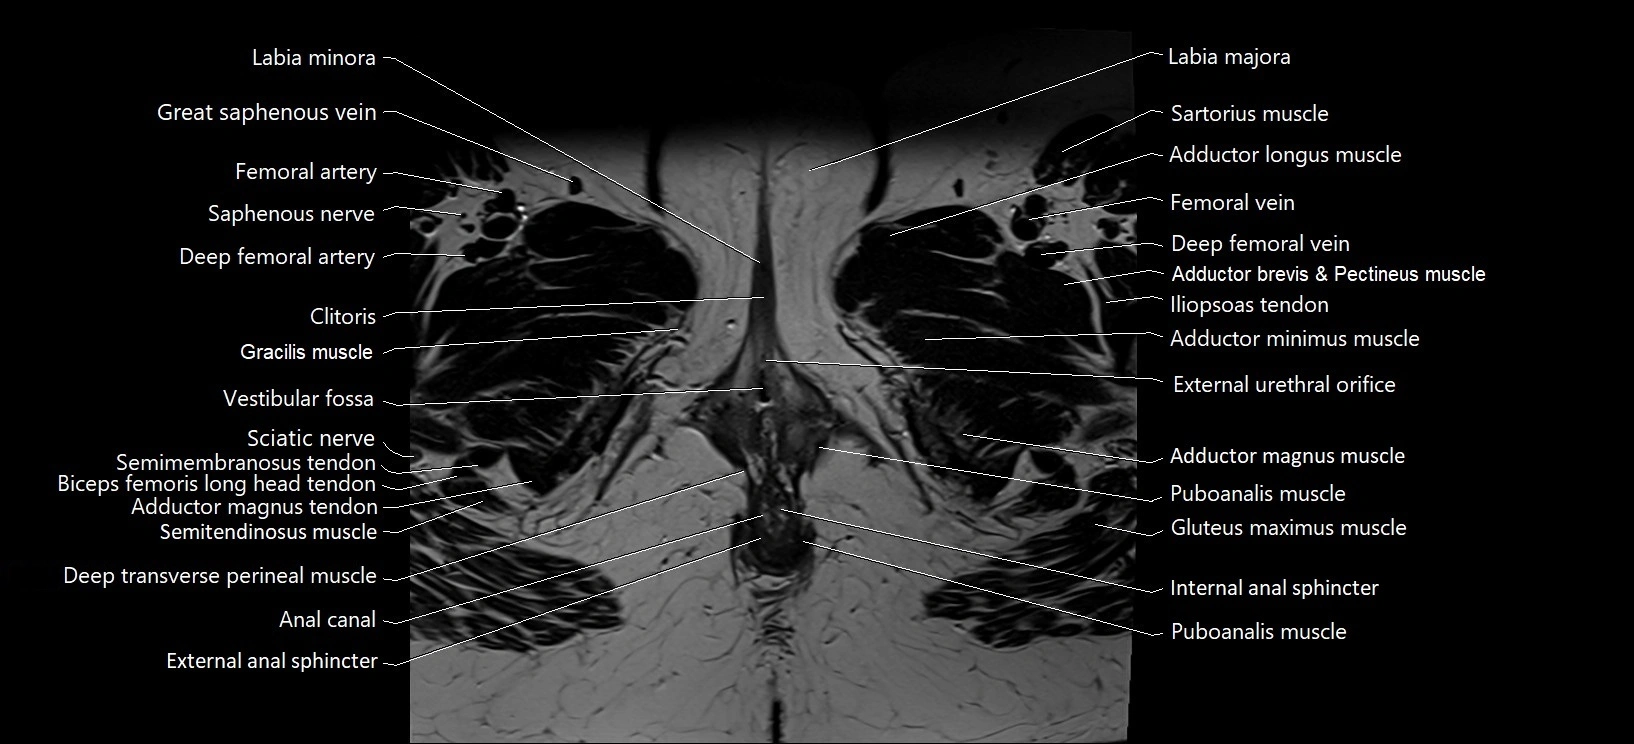

- Anal canal

- Clitoris

- Deep transverse perineal muscle

- External anal sphincter

- Femoral artery

- Femoral vein

- Gracilis muscle

- Internal anal sphincter

- Labia majora

- Labia minora

- Puboanalis muscle

- Puborectalis muscle

- Sciatic nerve

- Vestibular fossa